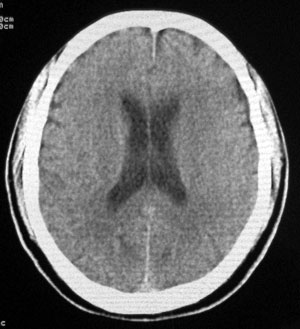

男性,65岁,头疼。 看看这大脑镰,ct值约83hu .

楼主的意思是让我们看大脑镰串珠样钙化,虽然ct值83hu ,也应该是钙化.(循环渐进).

感觉应该是生理性钙化

是生理性钙化